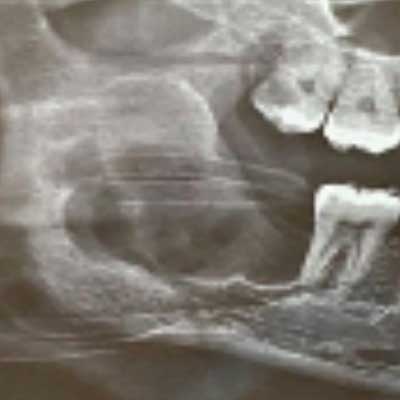

This is a representative case of an Odontogenic Keratocyst which was thankfully, caught early, during a routine dental xray (which is often the case)

Here we can see the entire cyst with its lining along with the tooth to which it was attached. Histopathological evaluation of the cyst revealed it to be an Odontogenic Keratocyst.